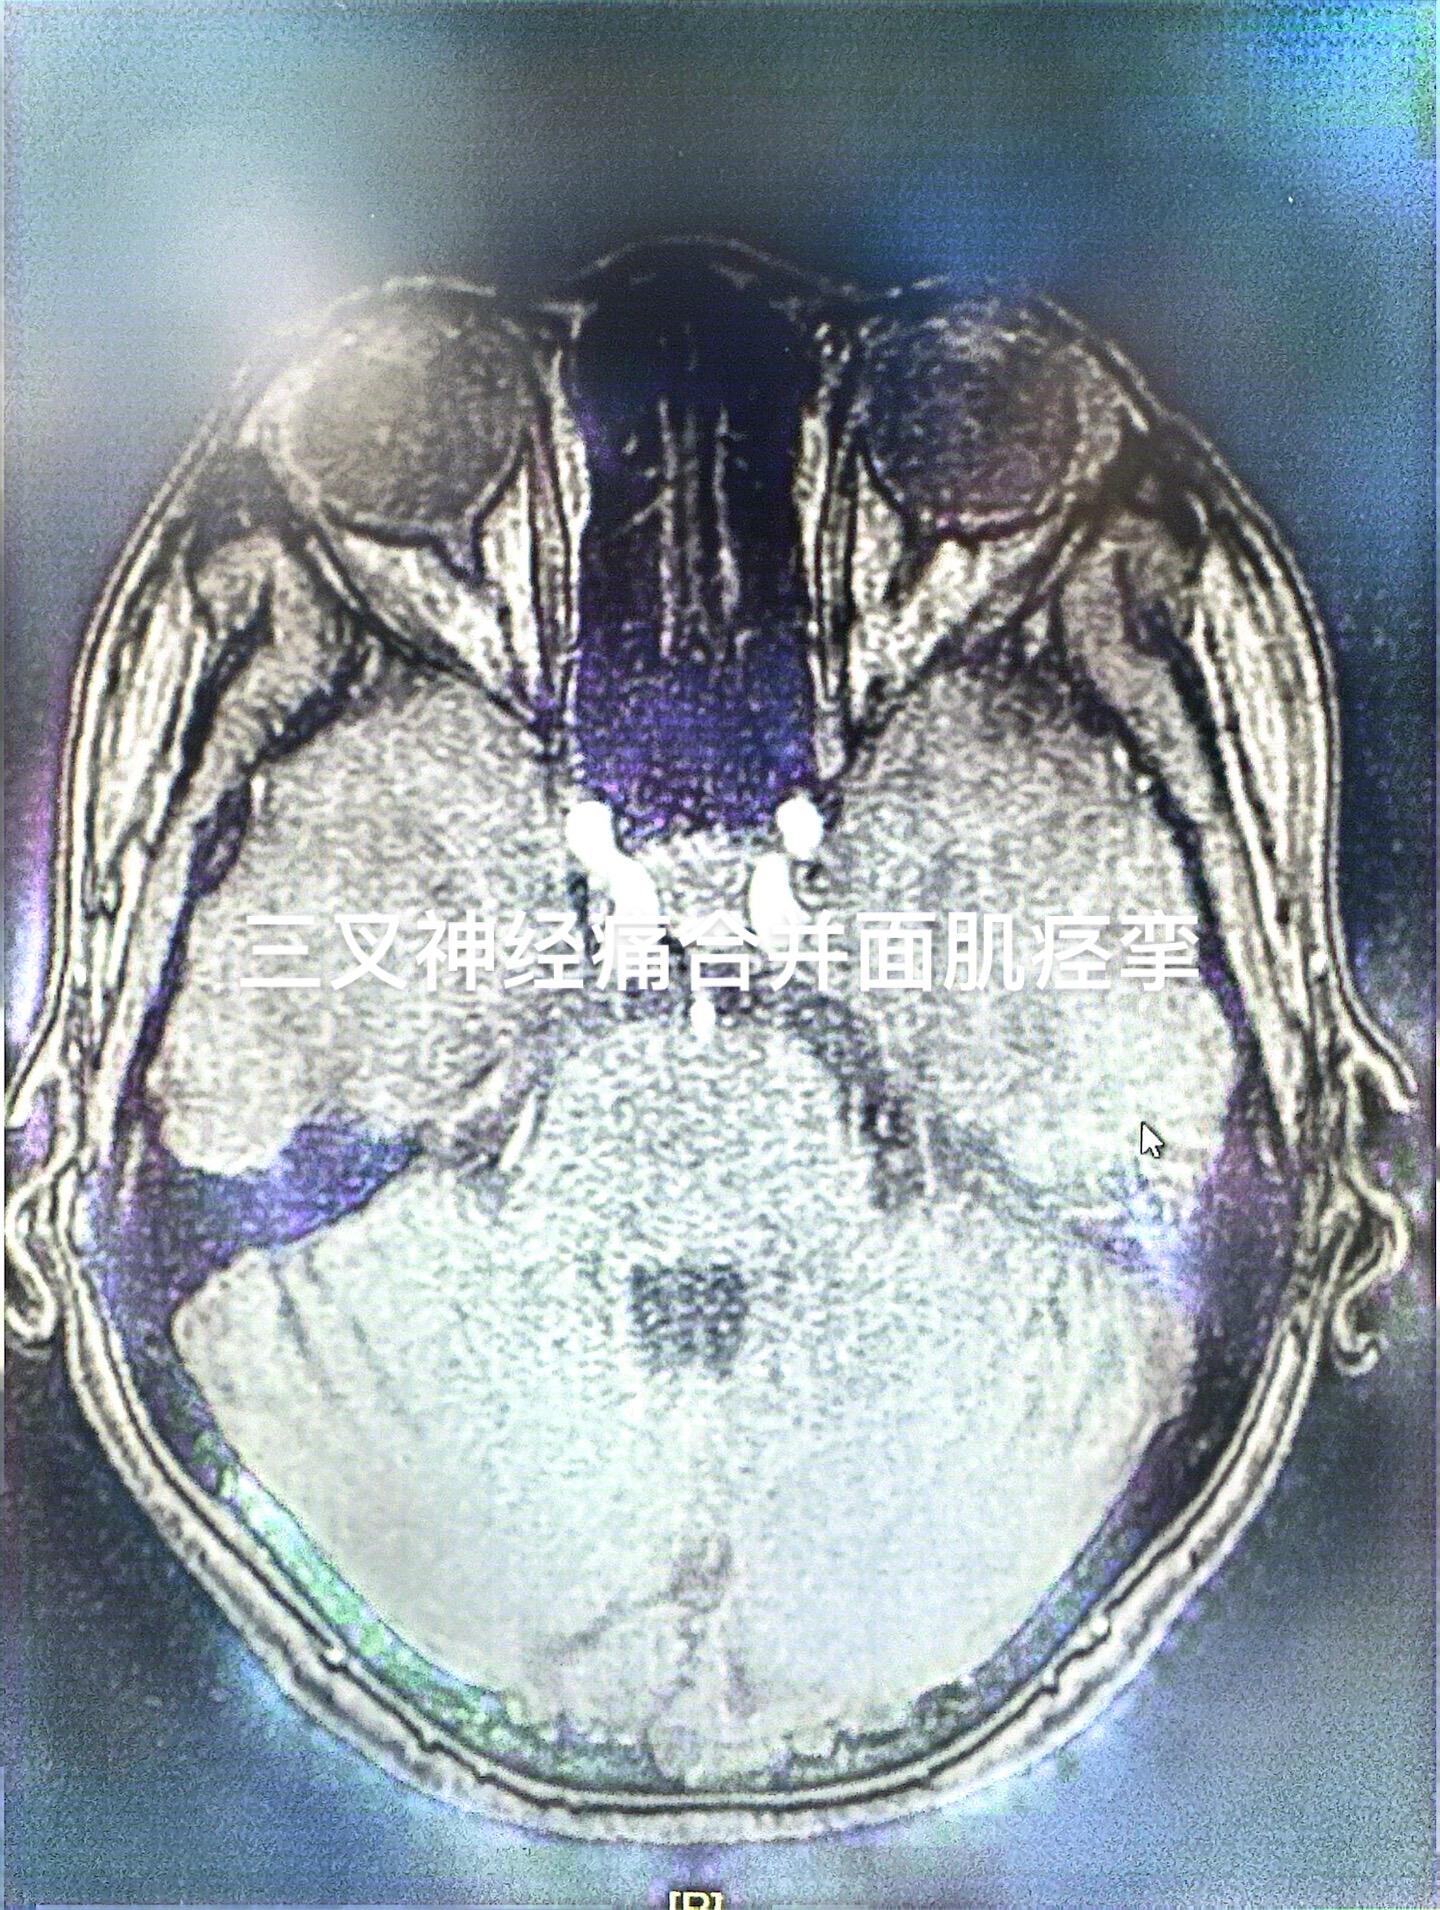

脸疼+脸歪是什么痛苦?本来疼已经很难受,再加上脸歪了简直是“雪上加霜”,一侧三叉神经痛,同时合并面肌痉挛,少见,但是偶尔会碰到,同一侧一个手术切口下一起处理!